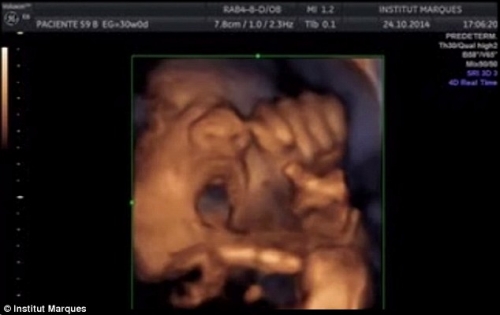

Chắc hẳn bạn sẽ thấy kì lạ! Một cái thai nhi mới được hơn chục tuần tuổi thì biết làm gì chứ? Nhưng những hình ảnh dưới đây sẽ cho bạn thấy điều bất ngờ này! Ít người biết rằng khi mới 16 tuần tuổi đã nghe được âm nhạc và thậm chí có thể mở miệng hát theo.

Đó là nghiên cứu được thực hiện và công bố bởi các nhà khoa học tại trung tâm nghiên cứu Institut Marques ở Barcelona, Tây Ban Nha. Cụ thể thai nhi khi 16 tuần tuổi đã có khả năng phát hiện âm thanh, phản ứng lại bằng cách cử động miệng và lưỡi.

Thai nhi 16 tuần tuổi đã biết hát theo nhạc.

Thí nghiệm được thực hiện trên phụ nữ mang thai giữa tuần thứ 14 và thứ 39 của thai kỳ. Phản ứng của thai nhi trong khi cho chúng nghe nhạc được ghi lại bằng máy siêu âm.

Khi tiếp xúc với âm thanh phát ra thông qua thiết bị babypod được đặt vào âm đạo, 87% thai nhi phản ứng, cử động đầu và chân tay, kèm với đó là miệng và lưỡi chúng chuyển động. Khi âm nhạc dừng thì chúng cũng dừng theo.

Có đến 50% thai nhi phản ứng rất rõ rệt, hàm và lưỡi chuyển động mạnh như đang cố nói hoặc hát theo.